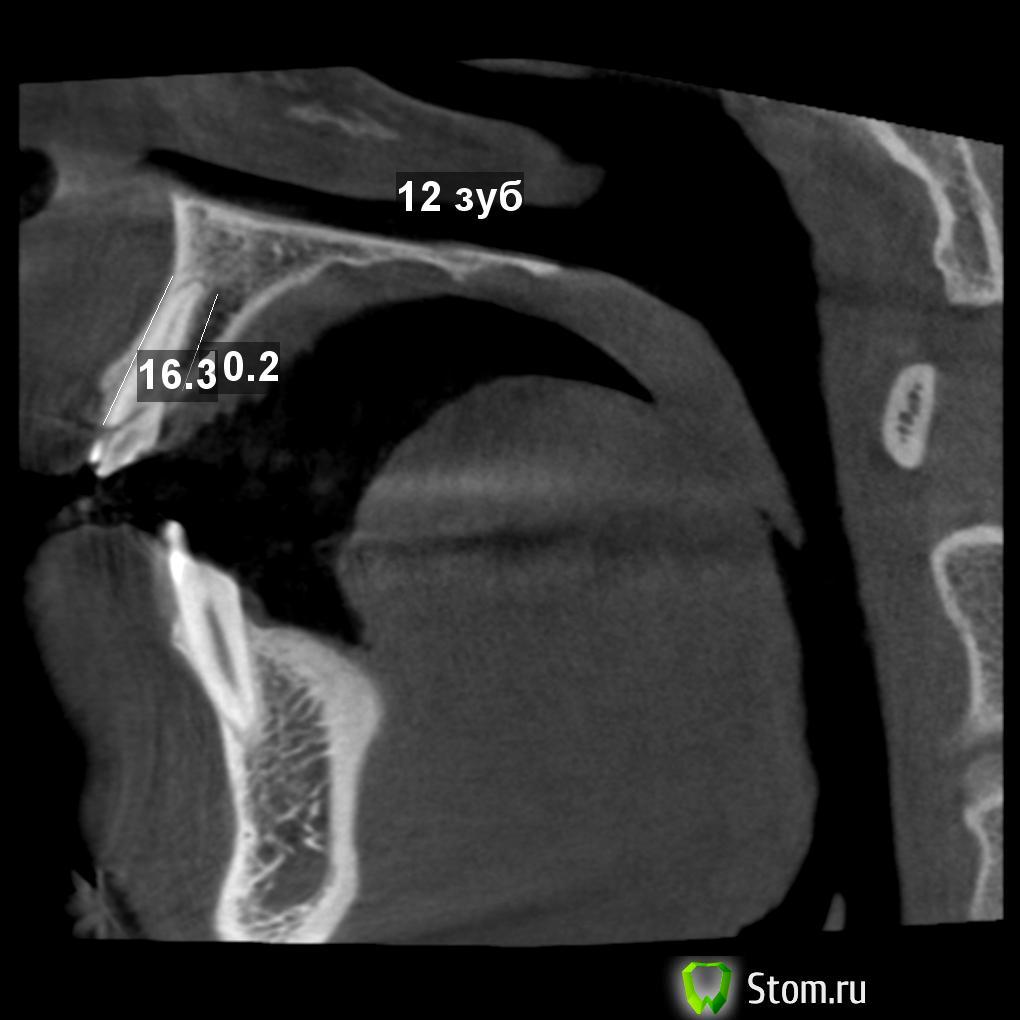

vitaliiPV Опубликовано 11 марта, 2012 Поделиться Опубликовано 11 марта, 2012 Здравствуйте уважаемые доктора. Поделитесь мыслью чтоб Вы сделали .Парню 20 лет , травме несколько дней. Подобных случаев у мене было мало, опыта в таком лечении тоже.Склоняюсь к удалению, хир. удлинение думаю нельзя из за коротких корней.Прислушаюсь ко всем комментариям.Помогите парню вернуть улыбку. Извините за качество фото снимал на телефон. После удаления отломка.12 зуб11 зуб Ссылка на комментарий